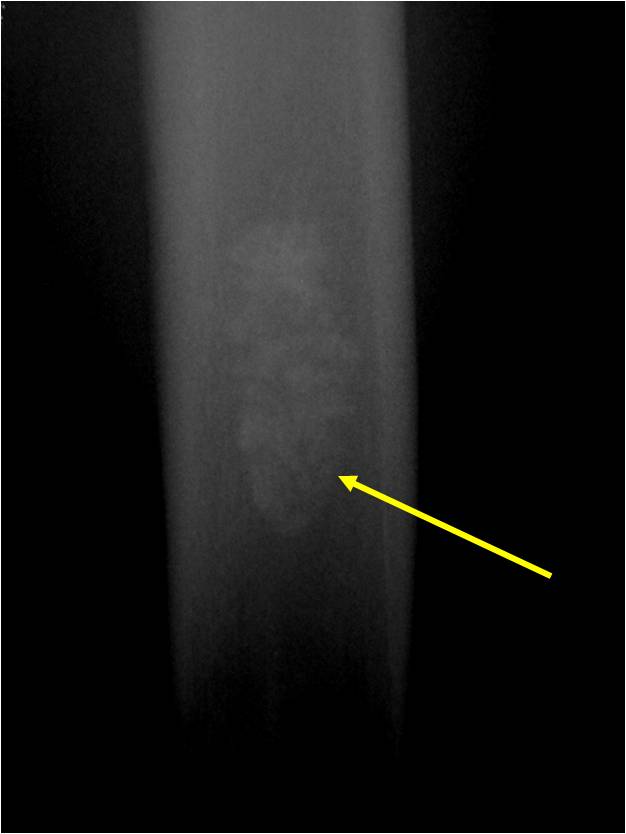

Radiographic Presentation

- Localized, radiolucent defect usually with punctate calcifications

- Calcifications are typical but not always present

- Matrix may demonstrate various degrees of calcification

- Calcifications are stippled, punctate, popcorn like calcifications and “Ring and Arc” calcifications

- Cortex may be scalloped and thinned in the phalanges

Plain X-Ray:

- Geographic lytic lesion

- Central often metaphyseal in long bones

- Expansile remodeling with thinned cortex

- Chondroid matrix with calcifications in majority of tumors

- Approximately 20% have limited or no calcifications

Geographic Lesion Bony Expansion Minimal Calcification Some Enchondromas do not calcify

Geographic lesion Stippled calcifications in lesion Phalanx is expanded Significant endosteal scalloping No cortical destruction No soft tissue extension Cortex Scalloped and Expanded